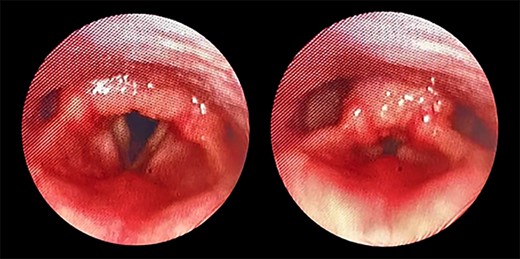

Transnasal flexible endoscope showing broad-based lesion affecting the middle two-third of the right vocal fold with a granular appearance of the interarytenoid region.

The patient maintained good oxygen saturation levels in room air with no signs of respiratory distress. She had a hoarse voice with a maximum phonation time of 10 s. Neck examination was unremarkable. Bedside transnasal flexible endoscope revealed bilateral vocal folds movement with polypoid lesions involving the middle two-thirds of the right vocal fold and the posterior part of the left vocal fold with edematous interarytenoid mucosa. Moreover, polypoid lesions were also seen in the base of tongue, epiglottis, with cobblestoning of the posterior pharyngeal wall (Figs 1 and 2). Basic laboratory tests were within the normal range. A contrasted neck computed tomography (CT) scan revealed bilateral asymmetric thickening of the vocal folds with medialization of the right vocal fold, with no enlarged cervical lymph nodes (Fig. 3).